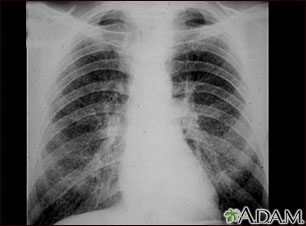

This chest x-ray shows stage II coal worker's pneumoconiosis (CWP). There are diffuse, small light areas on both sides of the lungs. Other diseases that may explain these x-ray findings include simple silicosis, disseminated tuberculosis, metastatic lung cancer, and other diffuse, infiltrative pulmonary diseases.